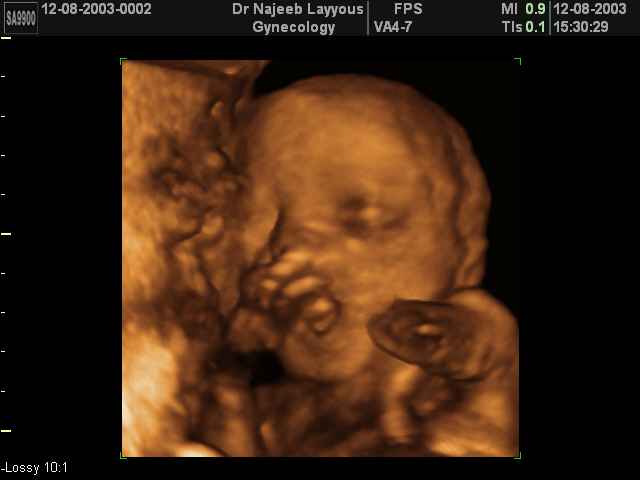

- تصرفات الجنين داخل الرحم

- صور لتصرفات الجنين داخل الرحم

صور لتصرفات الجنين داخل الرحم بجهاز الالتراساوند ثلاثي الأبعاد | الدكتور نجيب ليوس